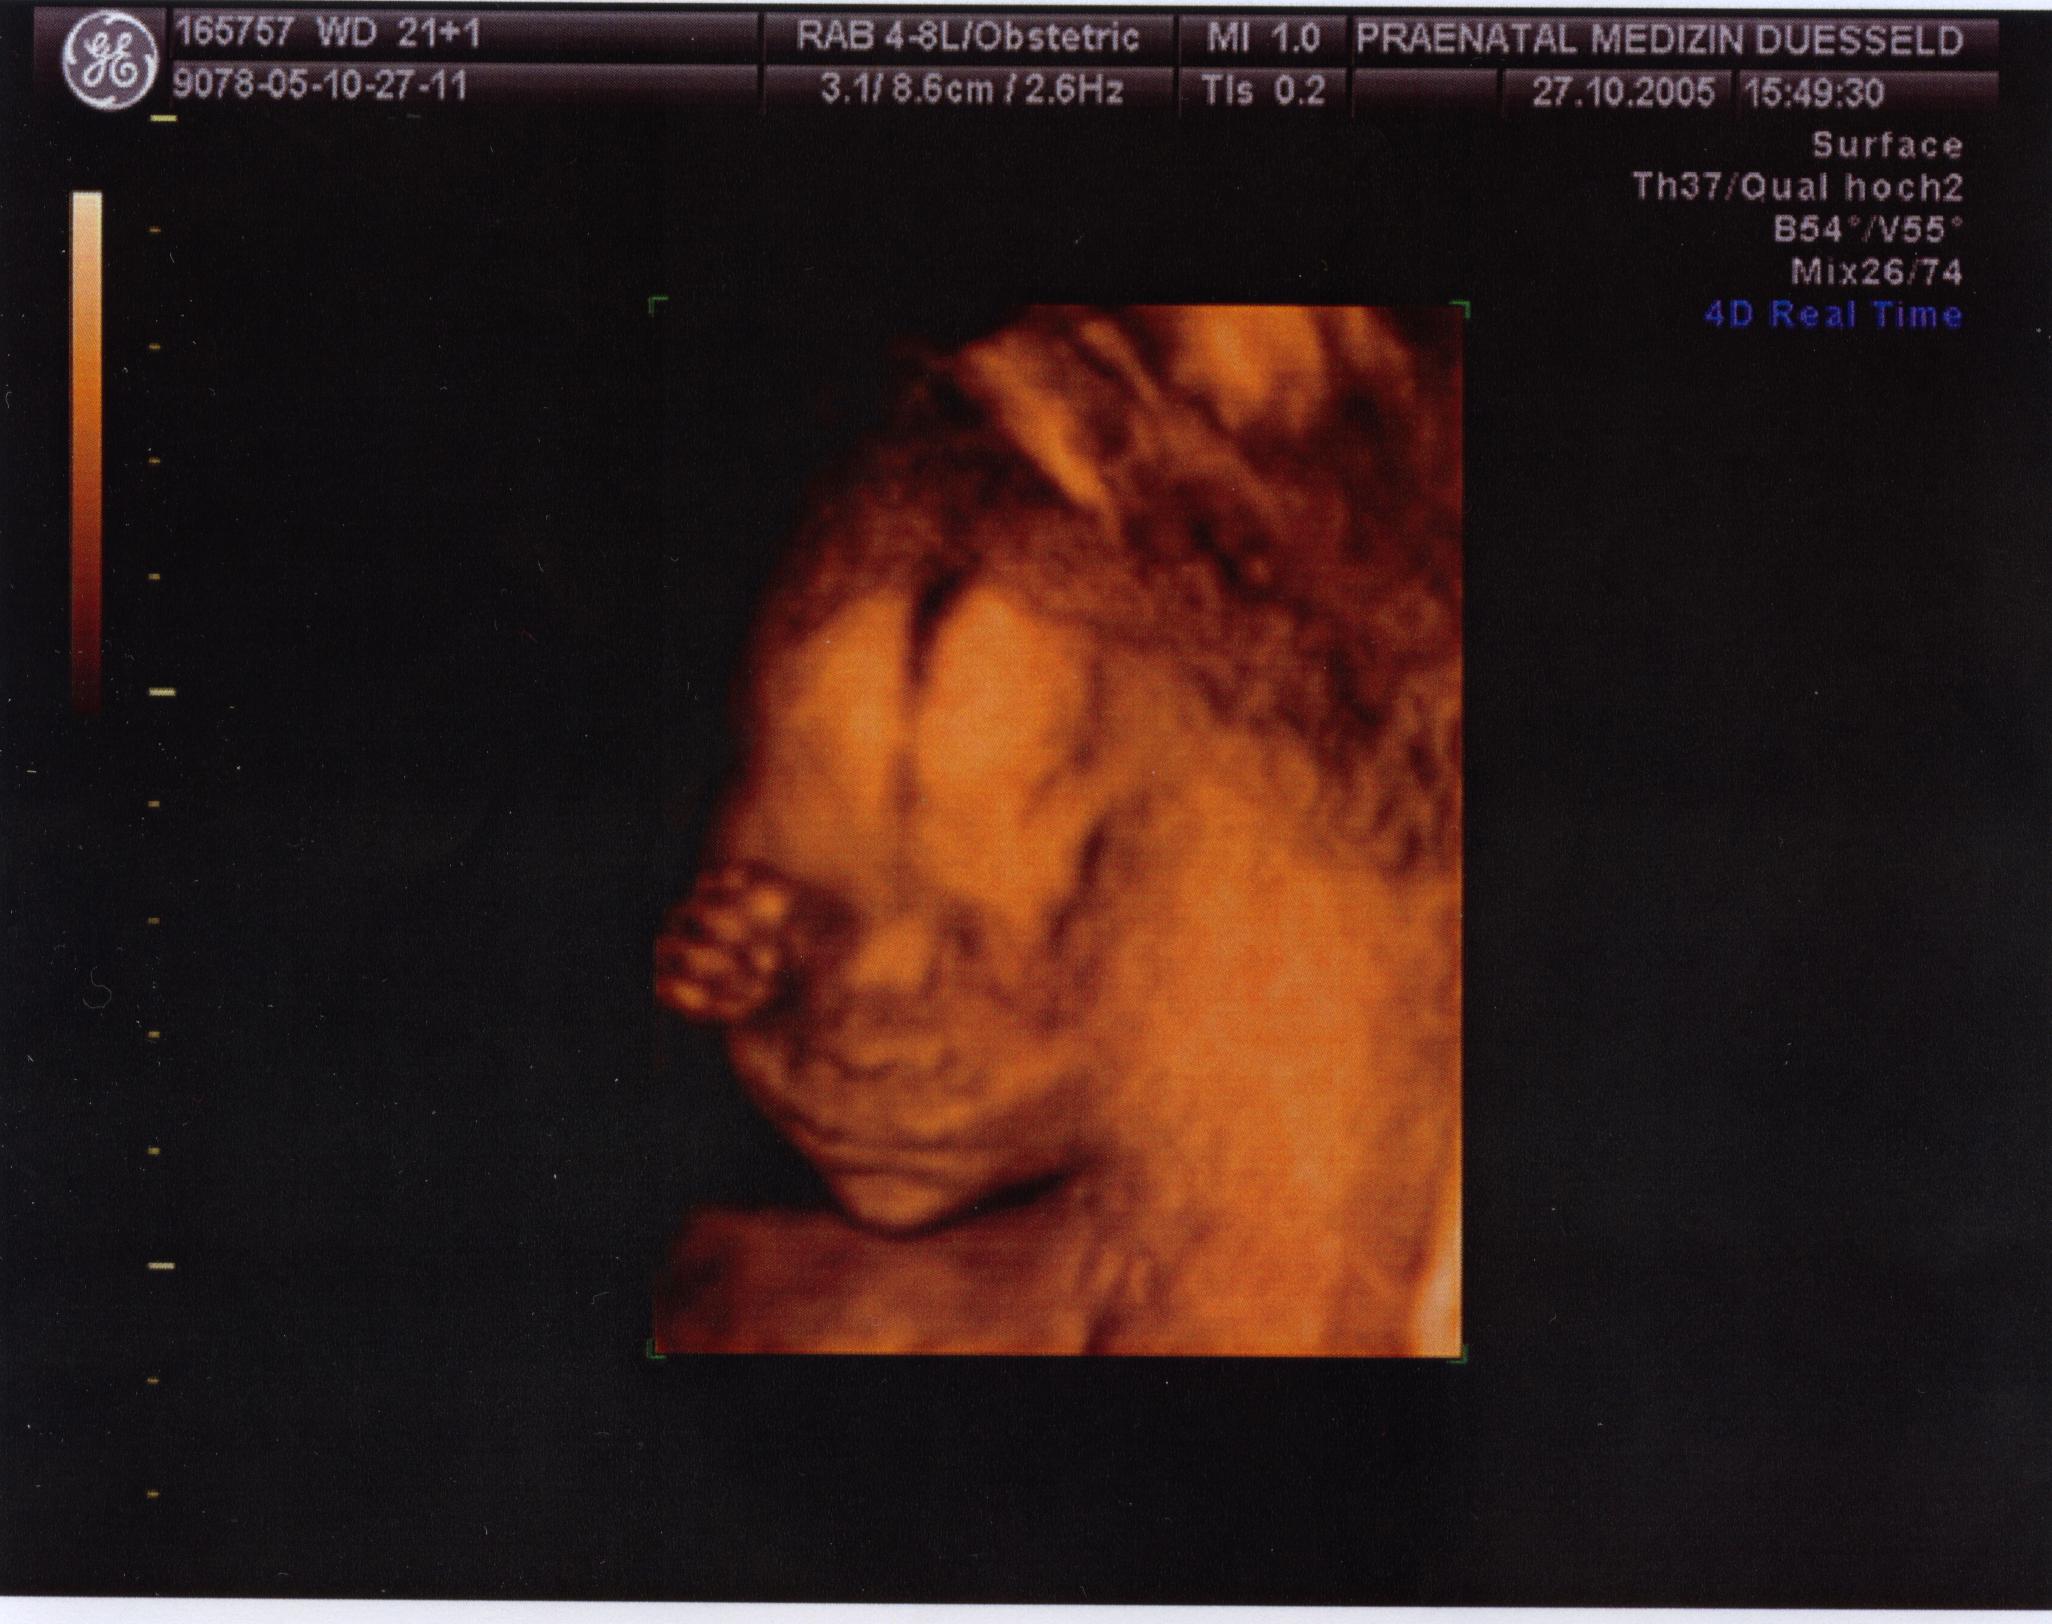

Doro meine Liebe,bald hältst du dein Glück in deinen Armen.Das ist echt klasse!!!!!! was du zur Renate gesagt hast ,da kann ich dir nur voll und ganz zustimmen. Dieser 3D Ultraschall,dass nennt man doch auch Organscreening,oder?Wollte das aufjeden Fall machen lassen,wird uns zwar sicher wieder was kosten,aber schitt drauf,finde das sehr sinnvoll.Obwohl mein Mann mittlerweile auf den Standpunkt steht,was soll das alles ,ist doch alles nur wieder zum bekloppt und Sorgen machen.Er würde am Liebsten in dieser Richtung nichts mehr machen.Denke es liegt daran,dass wir ja echt ziemlich lange jetzt auf das Ergebnis warten mußten und da macht man sich natürlich verrückt.Werde ihn aber schon überzeugen.In dem Bericht steht auch,dass sie eine Untersuchung empfehlen in ab der 15 /16 Woche auf z.B offenen Rücken und noch was ,weiß nicht mehr genau.So wie ich es verstanden habe,wird das auch durch Blutabnahme dann bestimmt. Mein Doc erwähnte das nicht......hmmmm

Hast du oder auch Anett das machen lassen? Werde ihn jedenfalls mal ansprechen.Kann man das dann auch 18/19 Woche rum noch machen,weiß das Einer von Euch?Da ist mein Männe im Moment auch gegen. Aber diese 3 Dinge fand ich bisher für mich wichtig,1. NFM,2. offener Rücken per Blutabnahme,glaube ich und 3. das Organscreening 3D oder auch Feinultraschall genannt,glaube ich .

Gerade 3D ,das hört sich so gut an und ich denke ,wie du schon sagst Doro,dass wir das nicht verpassen sollten.